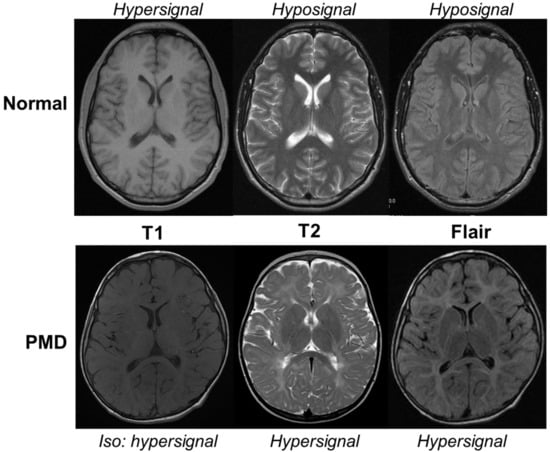

- Sarret, C.; Lemaire, J.-J.; Sontheimer, A.; Coste, J.; Savy, N.; Pereira, B.; Roche, B.; Boespflug-Tanguy, O. Brain Diffusion Imaging and Tractography to Distinguish Clinical Severity of Human PLP1-Related Disorders. Dev. Neurosci. 2018, 40, 301–311. [Google Scholar] [CrossRef] [PubMed]

- Girard, N.; Confort-Gouny, S.; Schneider, J.; Barberet, M.; Chapon, F.; Viola, A.; Pineau, S.; Combaz, X.; Cozzone, P. MR imaging of brain maturation. J. Neuroradiol. 2007, 34, 290–310. [Google Scholar] [CrossRef] [PubMed]